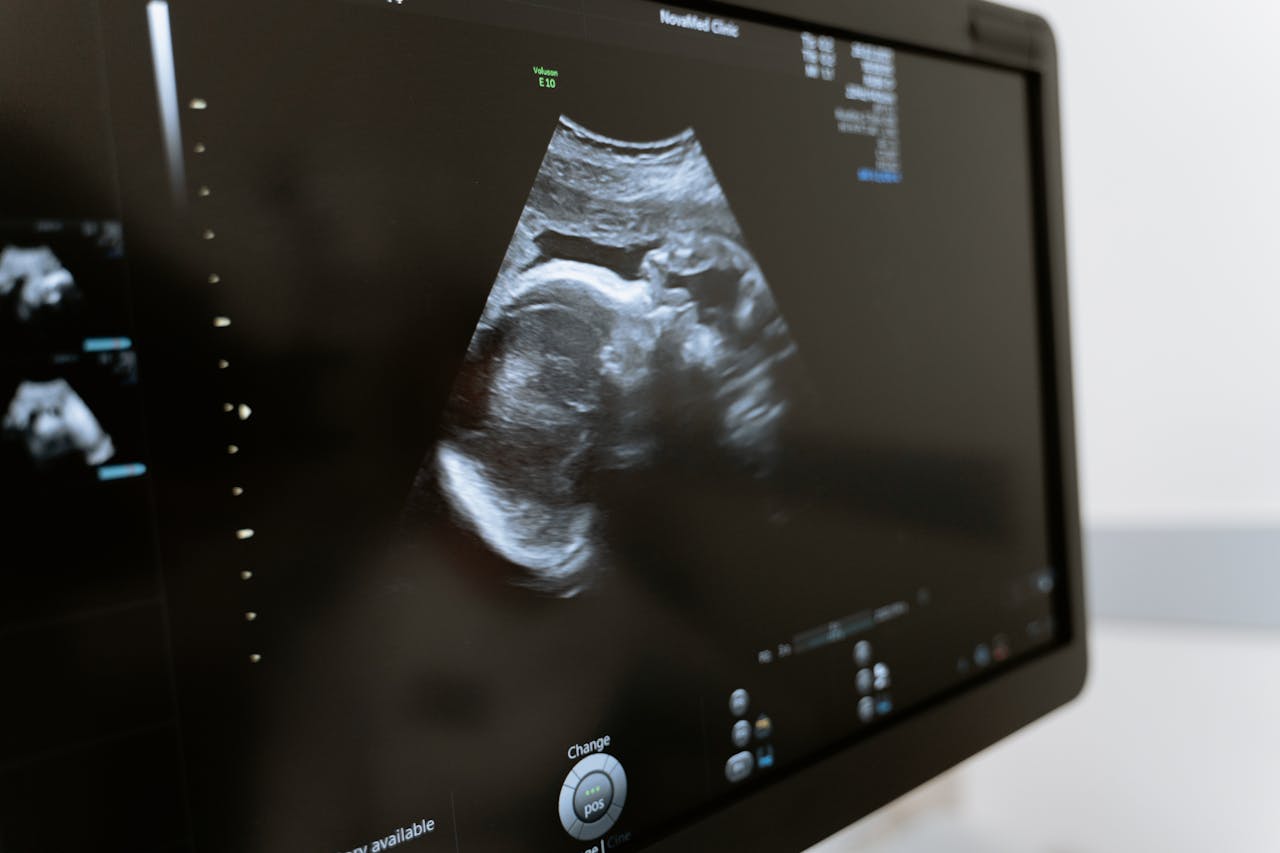

La salud femenina requiere atención continua y preventiva. Dentro de los controles ginecológicos más importantes, la citología anual (también conocida como prueba de Papanicolaou o